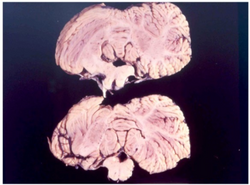

Cerebellum of a kuru patient